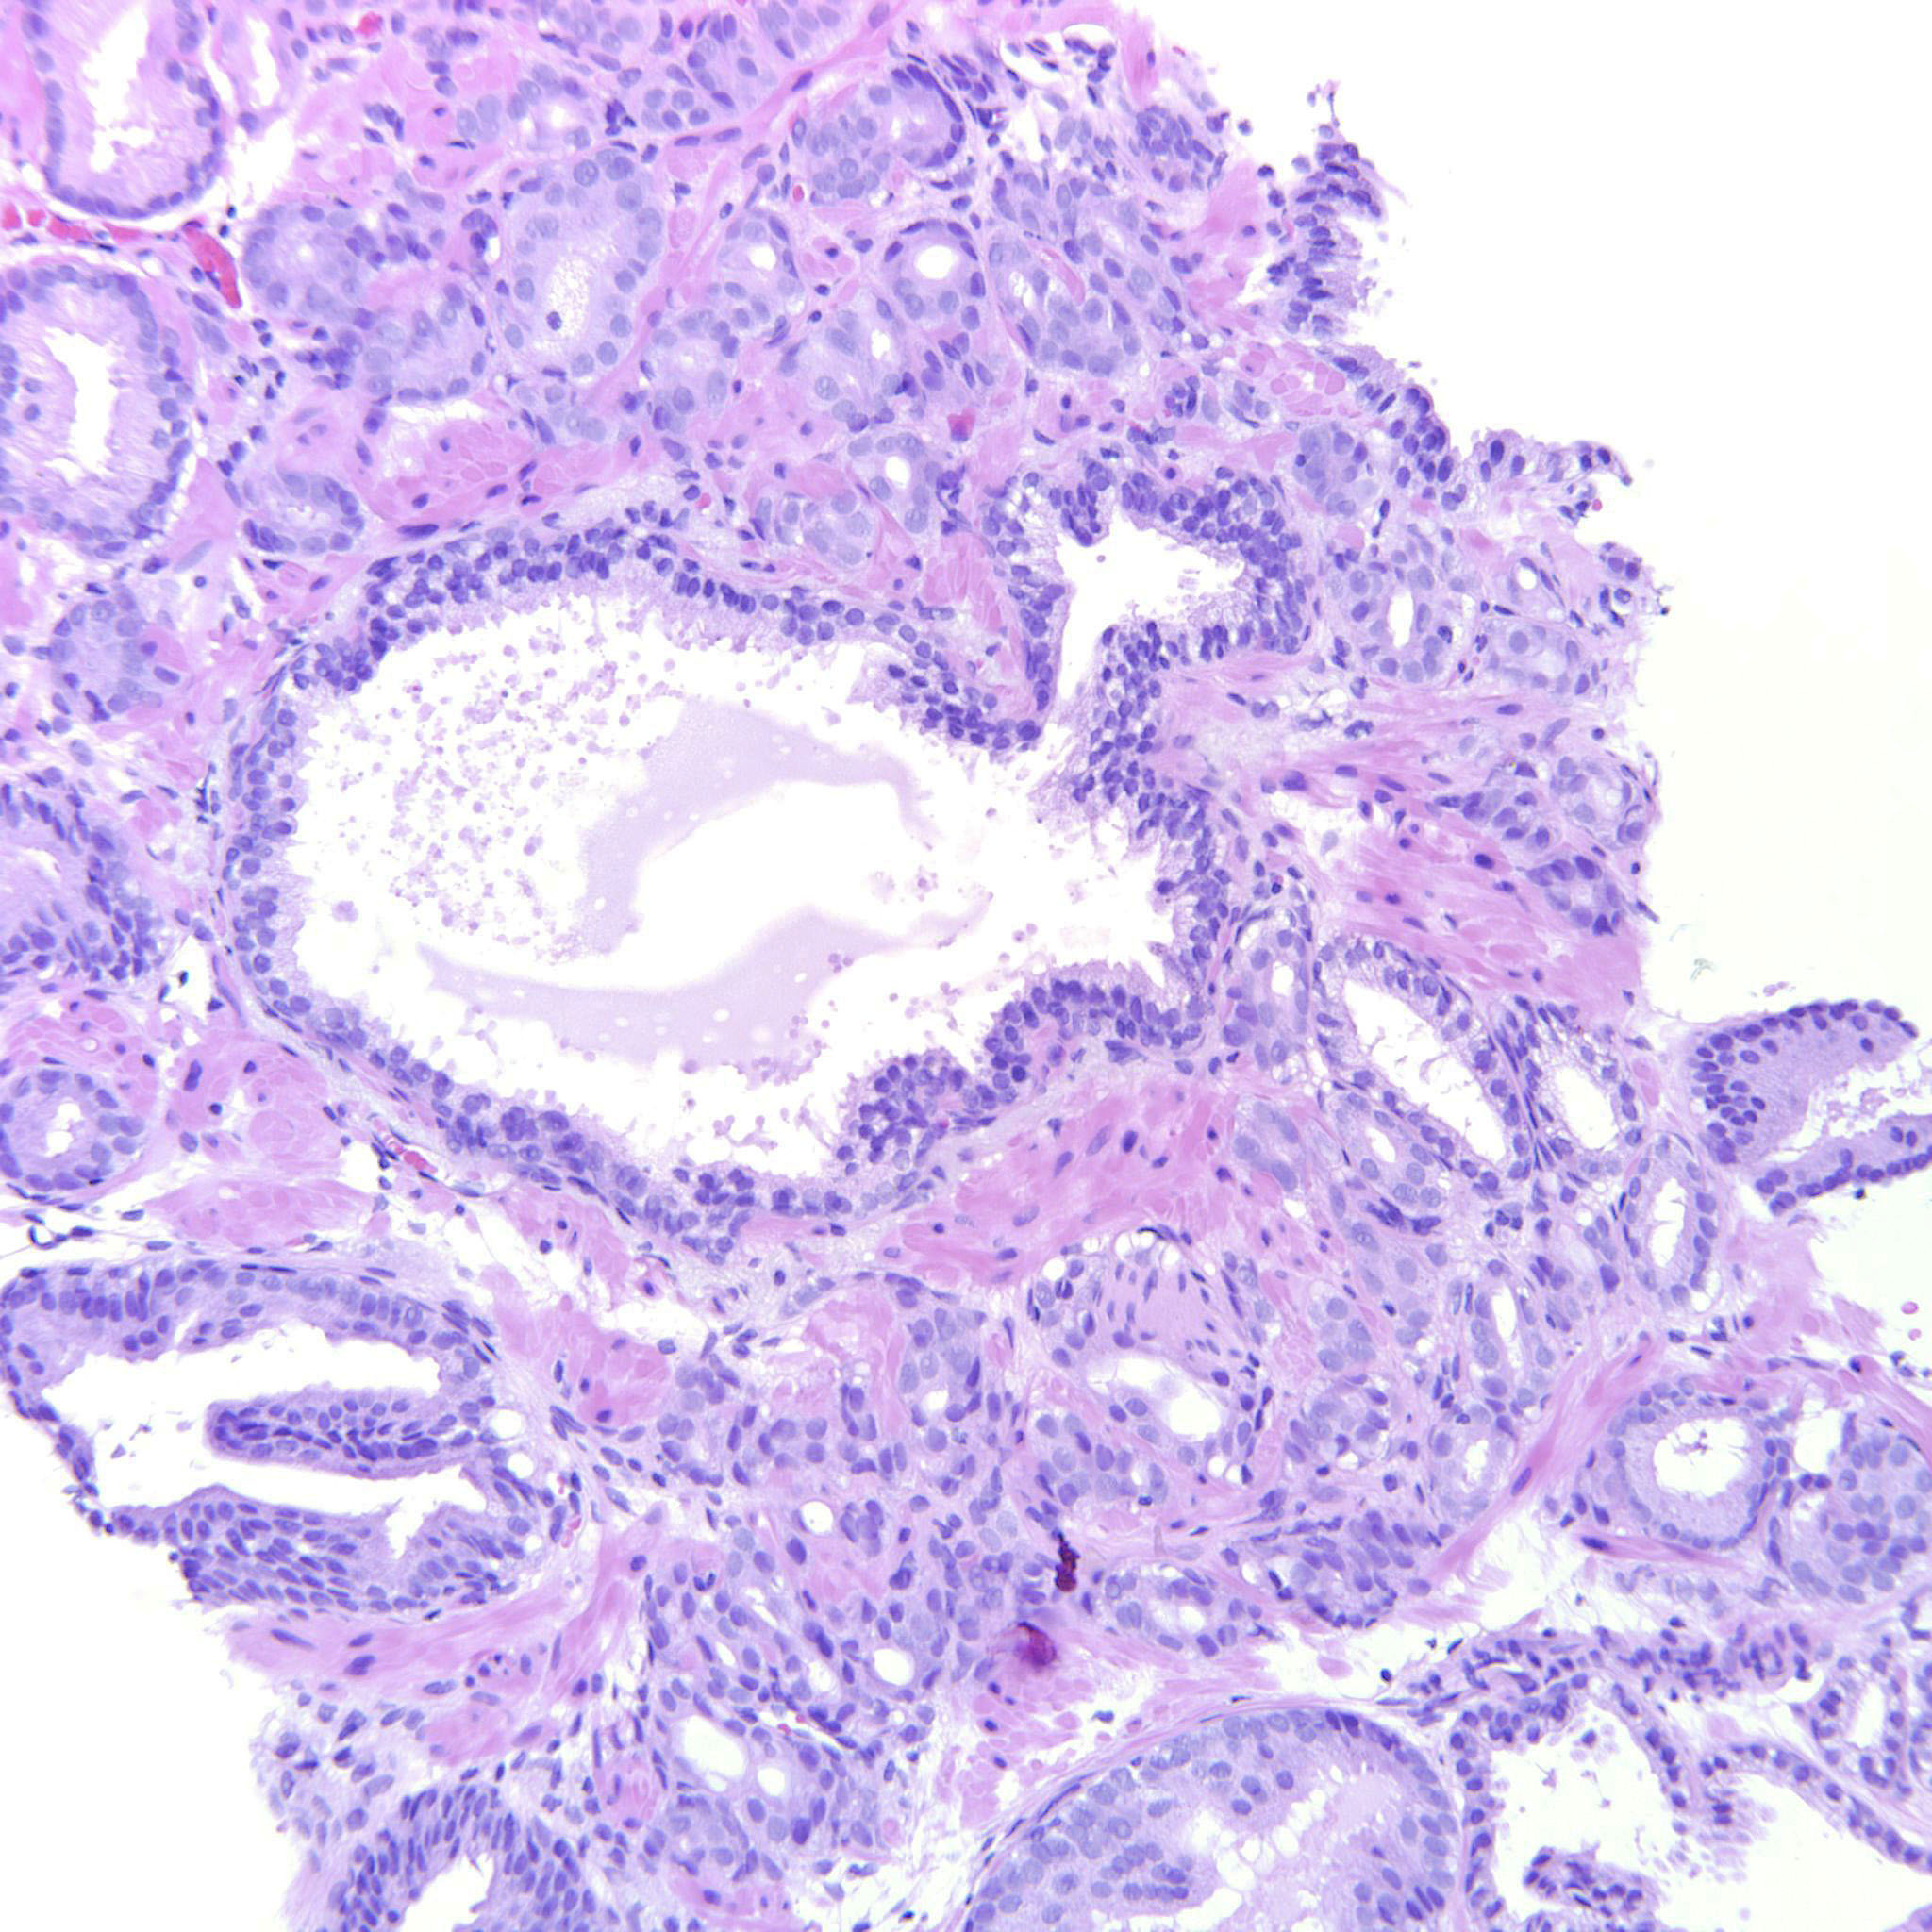

Prostate cancer grading

Case ID: 487